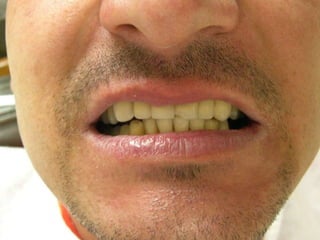

PRINCIPIOS ESTÉTICOSRestauraciones con forma, contorno y color adecuados

PRINCIPIOS ESTÉTICOSRestauraciones conforma, contorno y color adecuados